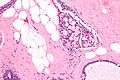

| Micrograph of collagenous spherulosis with the characteristic histomorphology - intratubular eosinophilic material with a spoke-like arrangement. H&E stain. | |

Collagenous spherulosis is characterized by a tubular/cribriform architecture with intratubular eosinophilic material that classically is arranged like the spokes of a wheel ("radial spikes"). There is usually no mitotic activity, and two cells populations (epithelial & myoepithelial) are present, like in benign breast glands.

The lesions are typically small (less than 50 spherules per lesion, less than 100 micrometers in size) and may be multifocal.